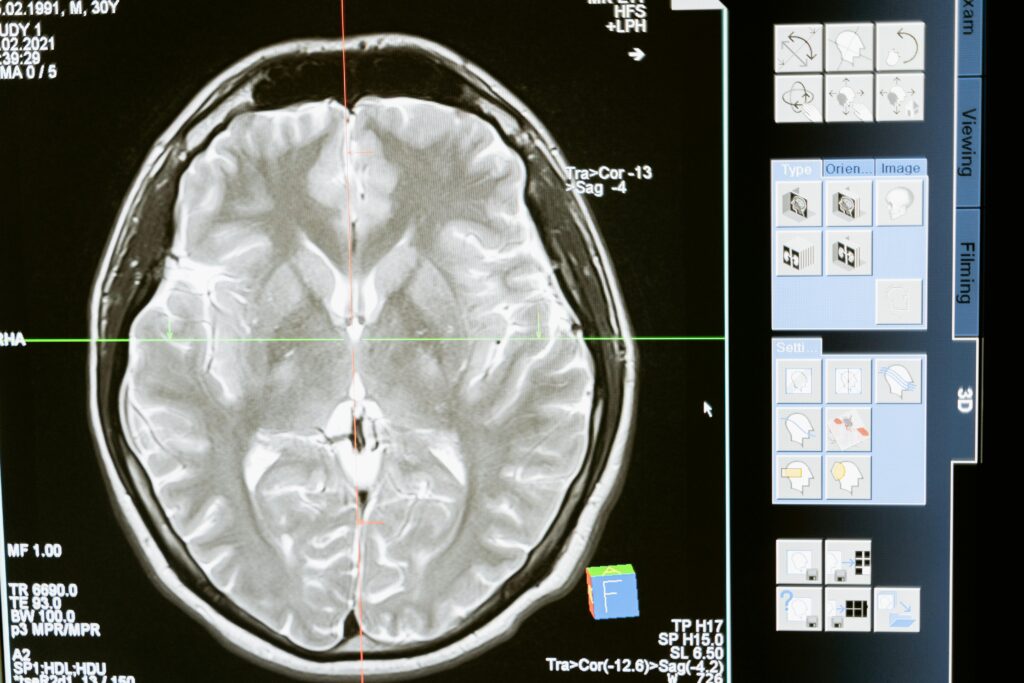

Diagnostyka – precyzyjne wykrywanie mikroskopijnych zmian

Diagnostyka gruczolaka przysadki wymaga zastosowania zarówno badań obrazowych, jak i szczegółowej oceny hormonalnej. Podstawowym badaniem obrazującym jest rezonans magnetyczny przysadki z kontrastem, który pozwala wykryć zmiany już od 1 mm. Mikrogruczolak w badaniu MRI widoczny jest jako owalna zmiana o pośrednim sygnale, która po podaniu środka kontrastowego wykazuje słabszy sygnał niż zdrowa tkanka przysadki.